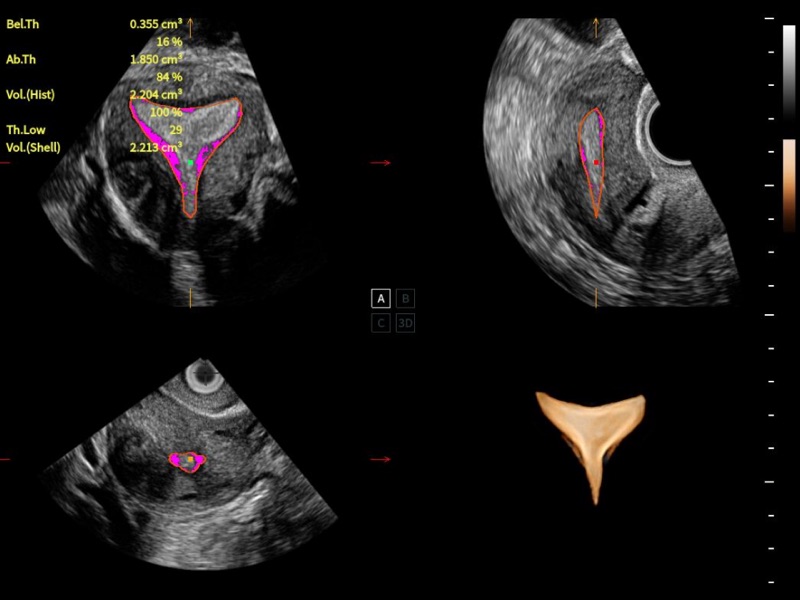

豐富的血流動(dòng)力學(xué)檢測(cè)技術(shù),可在不同醫(yī)療場(chǎng)景中高效捕捉血流信號(hào),助力臨床診療。

在傳統(tǒng)血流的基礎(chǔ)上優(yōu)化掃查和算法策略,能夠更好的抑制組織信息,提煉紅細(xì)胞運(yùn)動(dòng)信息,得到更高幀頻,高靈敏度和分辨率的血流信號(hào),還原更真實(shí)的血流動(dòng)力學(xué)。

通過(guò)光照模型,使二維血流顯示出立體的效果,增加血流的敏感性、成束性,減少外溢。可以和其他不同的血流技術(shù)聯(lián)合使用,融合不同技術(shù)的優(yōu)勢(shì)。輕松應(yīng)對(duì)微小血管,增強(qiáng)血流的立體效果,提升視覺(jué)敏感性。

通過(guò)創(chuàng)新的Matrix E自適應(yīng)濾波算法,能有效濾除軟組織和噪聲信號(hào),最大限度保留超低速微細(xì)血流的信號(hào);結(jié)合超長(zhǎng)時(shí)間域算法,極大提升細(xì)微血流的敏感性和空間分辨率,更真實(shí)的反應(yīng)組織、包塊的血流灌注情況。